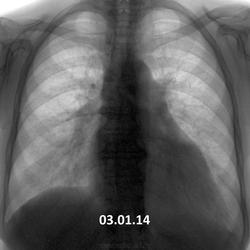

03.01.14 - острых жалоб нет, одышка. Летом лечила пневмонию. Предыдущая флгр. 05.02.13. Как относится к пневмотораксу справа - как к острому состоянию или, может,  как к состоянию после перенесенного пневмоторакса?

Это вчерашняя флюорография. Пациентка не лечилась.

Вы знаете,мне кажется подобная полоска "пневмоторакса" есть на всех трех снимках,только где-то более видна,а где-то-менее.Присмотритесь,может, кто-то тоже заметит.

Благодарю за динамику случая. Но у меня ещё меньше доверия осталось к пневмотораксу, который был или не был,.. осталось за кадром... (пред)настоящей истории этой.

Пневмоторакса не вижу. Подчеркнутая горизонтальная м/долевая плевра  справа. Сердце митральной формы за счет 2-й, 3-й дуги.

1. Мы уже не раз обсуждали здесь пневмотораксы...видели даже хронические.

3. Что ПРОТИВ шварты- одинаковая толщина...что для нее не характерно, в отличии от КРАЯ легкого.

А если приглядимся еще внимательнее,то и слева увидим подобную полосочку. Нет пневмоторакса.Подобный феномен почему-то чаше наблюдается у пациентов с обедненным легочным рисунком,фиброзных изменениях в легких.(это из личных наработок) С уважением,Миргалина

Контур «пневмоторакса» не нравится. Неровный он.

Линия, которая издалека принимается моим глазом за край поджатого легкого, при увеличении распадается на отдельные фрагменты легочного рисунка. На уровне 6-го, 7-го, 8-го рёбер этой линии нет вообще. Так что остаюсь при своем (втором на ветке) мнении – скиалогический феномен.

Разумеется, в заключении «скиалогический феномен» - не напишешь. И «усиление легочного рисунка с суммацией теней преимущественно по одной вертикальной линии правого легкого" – тоже не напишешь. Но и пневмоторакс – не напишешь. Похоже, осталось недоказанное подозрение на пневмоторакс. Как просто очень интересный случай.

Ну я бы не сказал. С 2006 г. читаю цифру ( а до этого 18 лет пленку крутил), таких вещей не видел. Всякие там неровности, особенно сердечной тени, аорты - да (даже на сайте обговаривали "укушенную" аорту Виктора Григорьевича). Поэтому тут и задумался. Все-таки, пневмоторакс был, и видимо саморазрешился.

И всё-таки его не было. Как сказал Коллега Дмитрий, не претендую на истину.) А феномен подобный скиалогический вполне могла дать кожная складка. Кожа разной плотности и толщины у всех нас была всегда.)